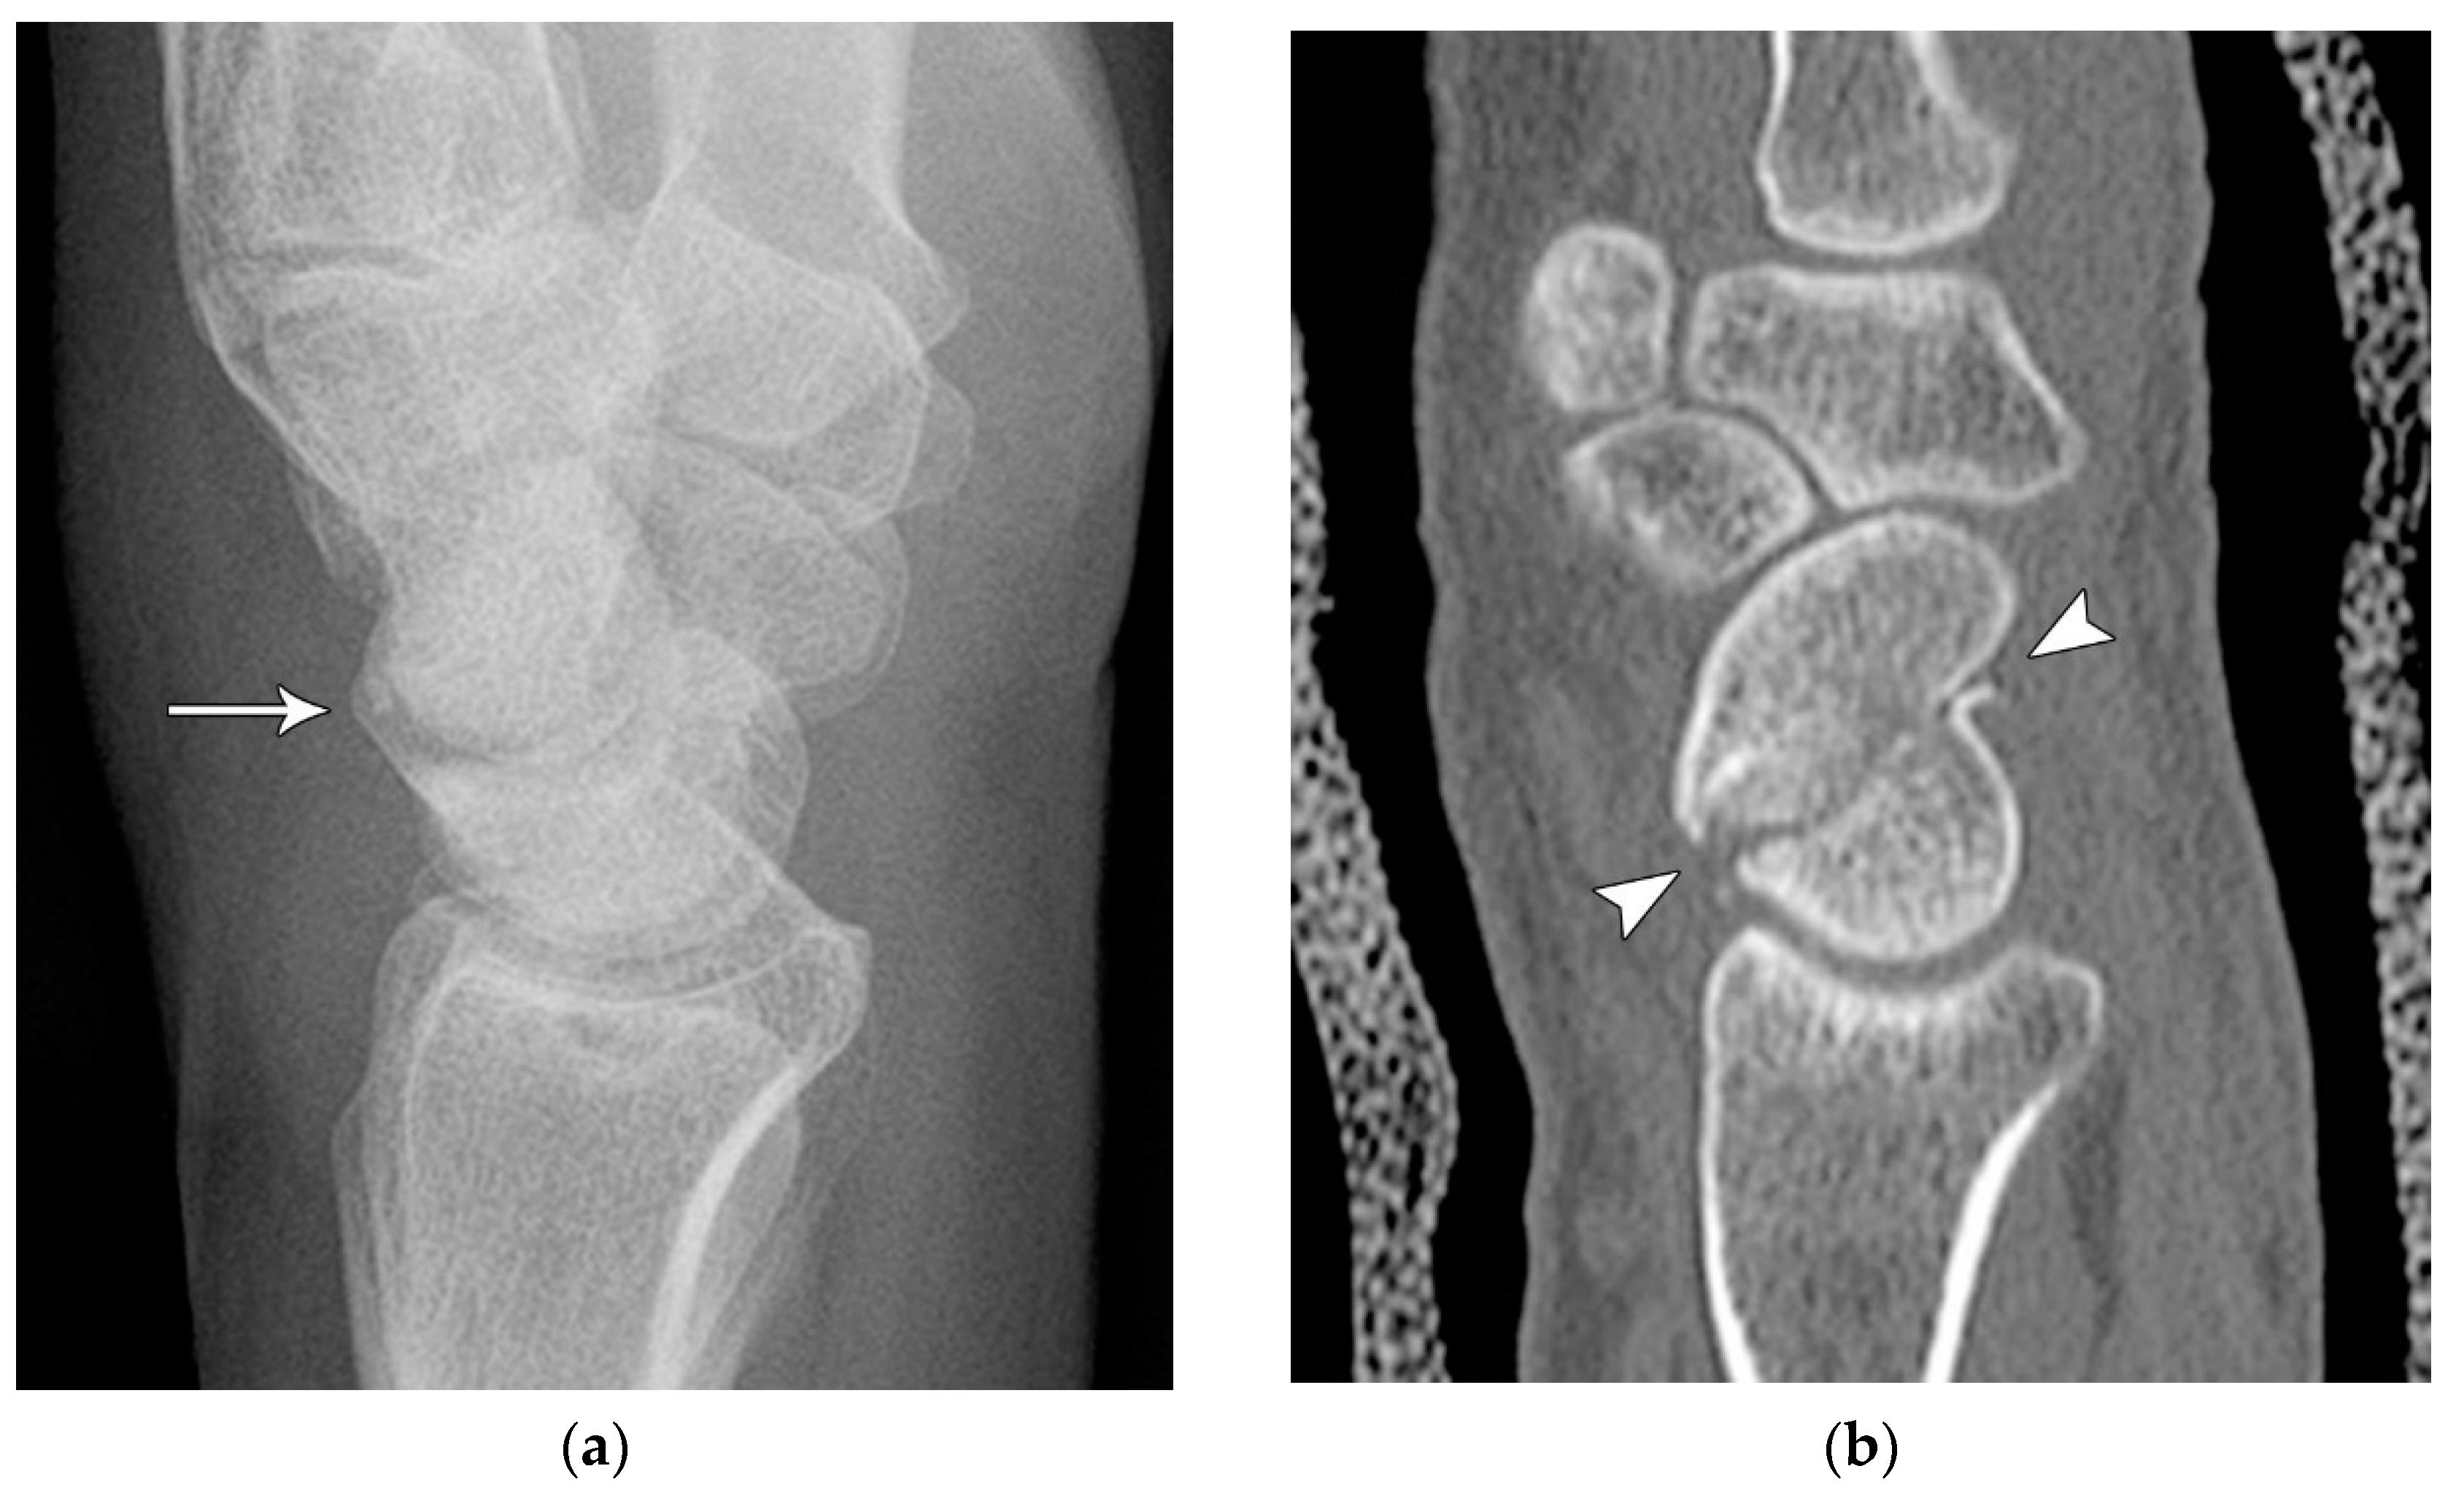

The majority of scaphoid fractures (70%) occur through the waist of the scaphoid, with 10% of scaphoid fractures involving the distal third, and 20% involving the proximal third (Figure 2 and Figure 3) [2,14]. With a scaphoid waist fracture, dorsal prominence at the fracture site due to dorsal angulation is known as humpback deformity (Figure 4). This deformity is important to recognize, as it needs to be more aggressively managed due to high risk of nonunion [15]. Additionally, if the two fragments unite with a humpback deformity, it may further destabilize the wrist. This humpback deformity may also be associated with dorsal intercalated segment instability (DISI), which will be covered in more detail later.

Figure 4. (a) Lateral radiograph of the wrist showing Humpback deformity (arrow) after a scaphoid fracture. (b) Sagittal CT reformation of the wrist showing the full extent of a humpback deformity with dorsal prominence at the site of the scaphoid fracture (arrowheads); image courtesy of Frank Gaillard, Radiopaedia.org, rID: 18269.